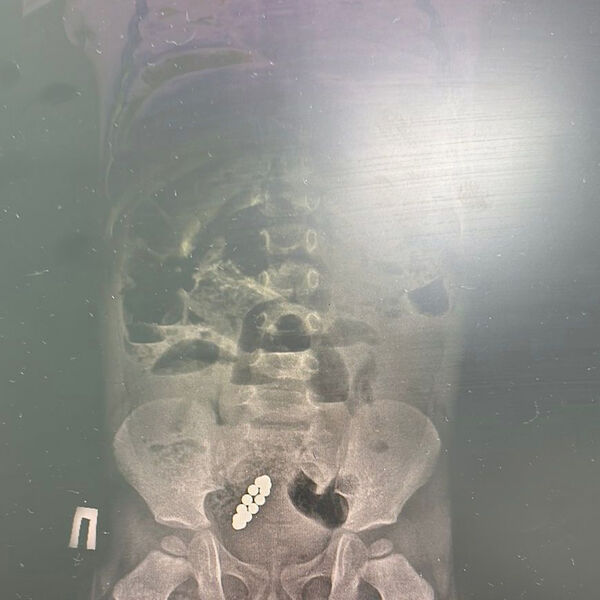

Тянули с больницей: ребенок жил с 13 магнитами в ЖКТ девять дней

В Казахстане спали ребенка с 13 магнитами в кишечнике, он жил с ними девять дней

Врачи Центра детской и неотложной помощи в Алматы (Казахстан) спасли семилетнего ребенка, который больше недели проходил с 13 магнитами в кишечнике. Об этом сообщили в пресс-службе медицинского учреждения.

По информации врачей, мальчик почувствовал недомогание 27 января. Родители отвезли сына в частную клинику, где на рентгене увидели магниты и рекомендовали обратиться в больницу. Но родители приняли решение «наблюдать за состоянием ребенка самостоятельно» и повторно показали сына врачам через девять дней, когда у него началась рвота до 15 раз в день. Мальчика экстренно госпитализировали в Центр неотложной помощи.

«Диагноз – острая низкая кишечная непроходимость и инородное тело в желудочно-кишечном тракте. Нам пришлось выполнить две сложные операции», — рассказал хирург медучреждения, добавив, что из кишечника мальчика удалили 13 магнитов.

Медики отметили, что маленького пациента выписали, ребенок чувствует себя хорошо.